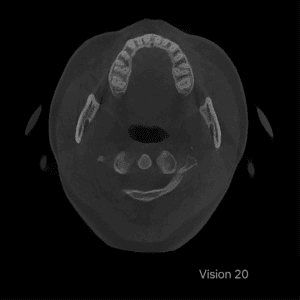

Vision 20 is an advanced CBCT imaging system that is capable of Panoramic X-Ray, Cephalometric, as well as 3D facial scanning, allowing the clinician to capture comprehensive view of the patient’s oral health.

Vision 20 supports Free FOV, allowing for flexible adjustment from 4x3cm to 20x20cm FOV according to the clinical purpose. It can be utilized in various medical fields, including implant treatment, periodontal treatment, orthodontics, and TMJ treatment.